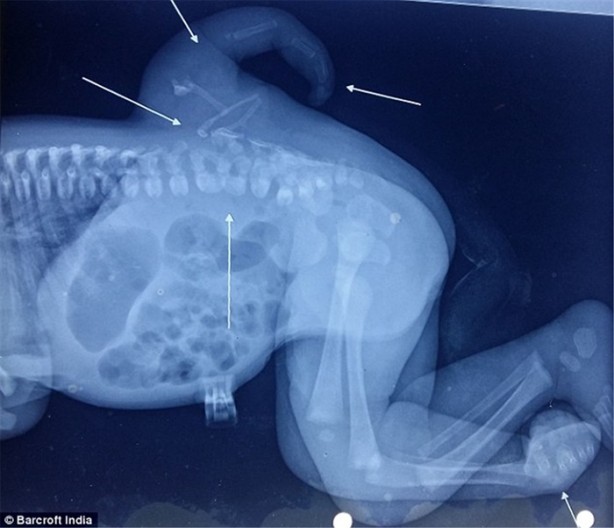

İki yaşındaki Varsha Sena milyonda bir görülen bir durumla dünyaya geldi.

Sırtında gelişen bu eklem yaşamını olumsuz etkiliyordu.

Operasyonu yapan Dr. Daljit omuriliğe bağlı olarak oluşan eklem ile ilk kez karşılaştıklarını belirtti.

Dr. Singh ve takımı ameliyatı başarılı olarak tamamladılar. Böyle bir durumla 50 yıldır hiç karşılaşılmadığını söyledi. Dr. Singh ve takımı kısa bir süre içerisinde rahatsızlık veren bu eklemi operasyonla alabileceklerini söyledi.

Hamilelik sırasında, hücrelerin embriyonik gelişimi anormallik gösterirse polymeliaya sebep oluyor.Fotoğrafta operasyondan sonra istenmeyen bacağın başarılı olarak alındığını görebilirsiniz.